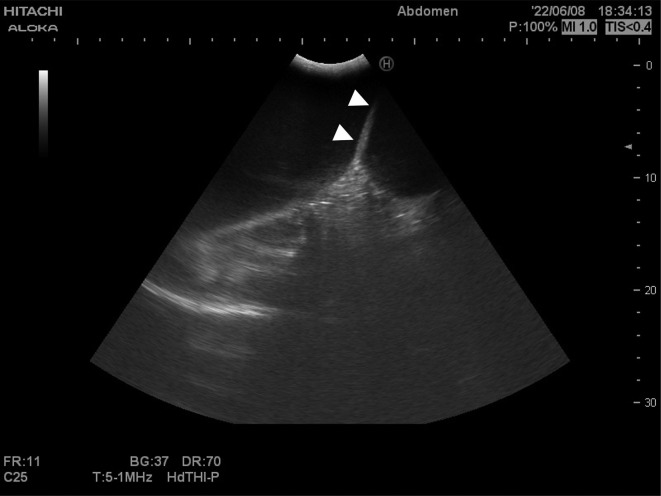

A male foal developing within a pregnant native Hokkaido mare presented with an abnormal bladder on gestational day 215 and was delivered by inducing parturition. Transabdominal ultrasonography indicated a bladder depth of >13 cm, with a wall-like structure bisecting the bladder. At 42 hr after birth, transnasal endoscopy revealed a cleft hard palate, and the foal was subsequently euthanized. A defect in the palatine process of the maxillary head and a large cyst connected to the bladder, although not continuous with the umbilicus, were identified by autopsy computed tomography and necropsy. The foal was accordingly diagnosed with a cleft median hard palate and urachal dysplasia.